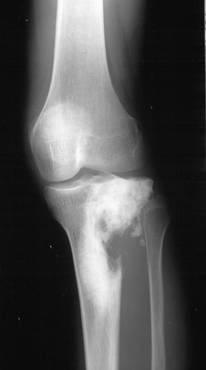

b)   Tumora cu mieloplaxe (celule gigante) – se intalneste exclusiv la adulti, afectand mai ales femeile. Are sediu epifizar, predilect langa genunchi si realizeaza o imagine transparenta, excentrica ce umfla osul. Imaginea descrisa are o structura neomogena data de travee opace ce dau un aspect de fagure tumorii. Corticala este impinsa in afara si subtiata. Trecerea intre tumora si diafiza sanatoasa are loc brusc, dand compactei un aspect amputat

Fig. 84 – Tumora cu mieloplaxe